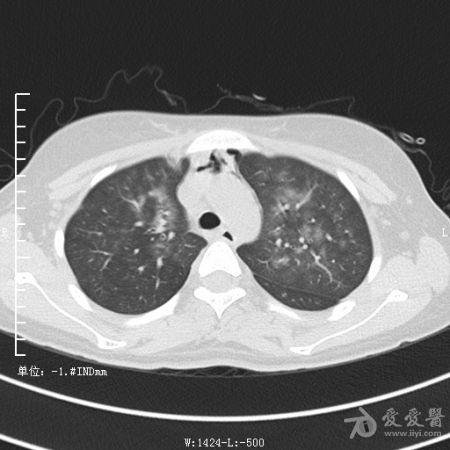

典型支气管扩张及肺水肿CT片

典型支气管扩张肺水肿